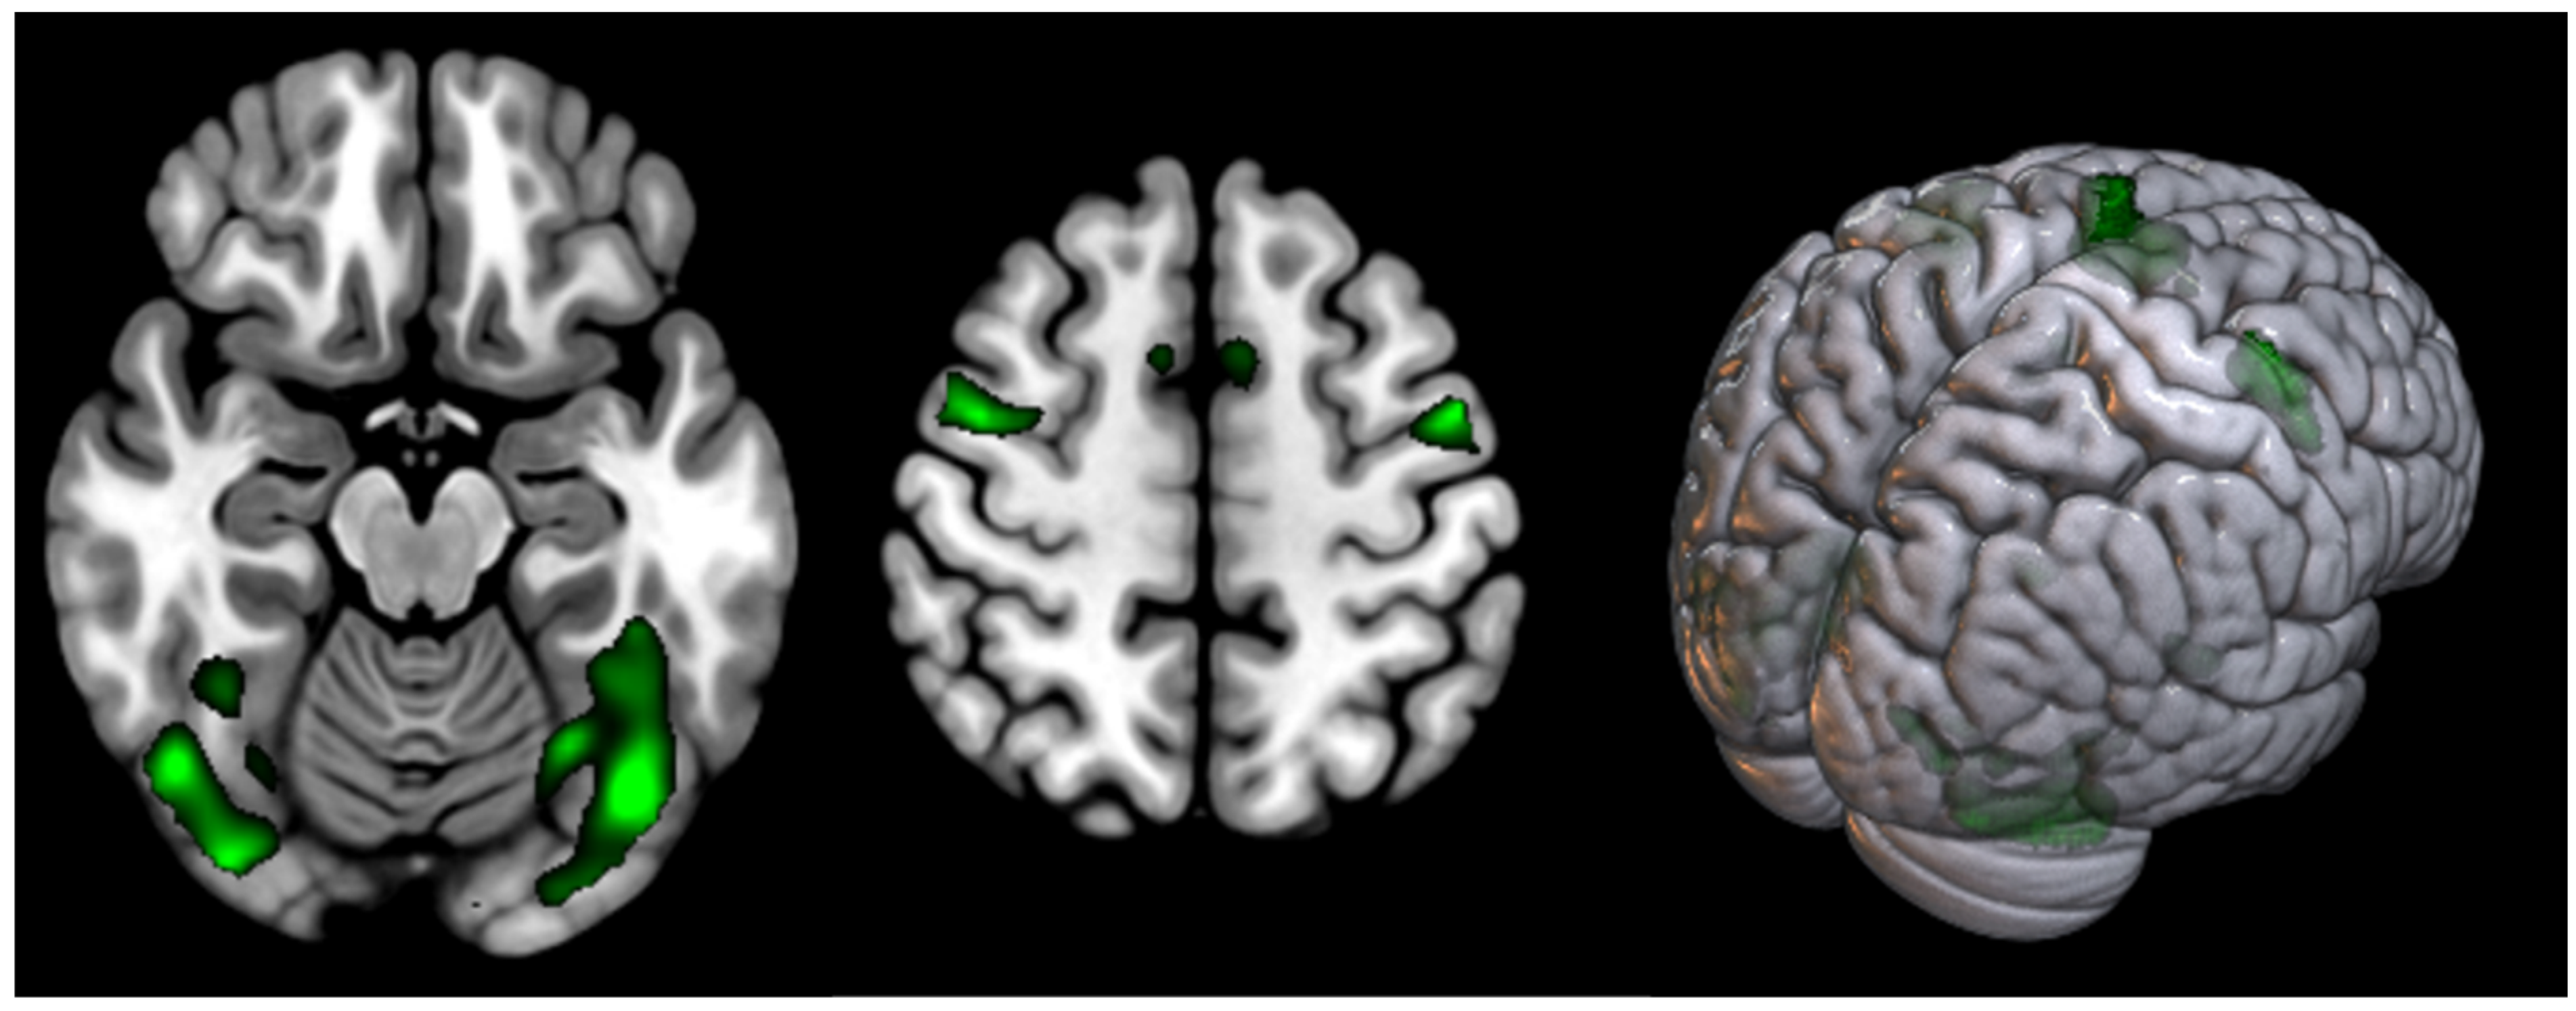

| T | PFWEcorr | Number of Voxels | Peak MNI Coordinate | |

|---|---|---|---|---|

| Supplementary motor cortex | 11.98 | <0.000 | 799 | 0 0 68 |

| Occipital cortex (Fusiform gyrus) (L) | 10.34 | <0.001 | 1507 | 60 8 30 |

| Occipital cortex (Fusiform gyrus) (R) | 9.24 | <0.005 | 706 | 44 −66 −20 |

| Precentral gyrus (L) (BA6) | <0.007 | 608 | −54 −2 48 | |

| Precentral gyrus (R) (BA6) | 8.67 | <0.009 | 221 | 42 −2 56 |

| T | PFWEcorr | Number of Voxels | Peak MNI Coordinate | |

|---|---|---|---|---|

| Supplementary motor cortex | 10.98 | <0.000 | 1002 | 2 8 58 |

| Occipital cortex (Fusiform gyrus) and Cerebellum Posterior Lobe (L + R) | 16.96 | <0.000 | 13,405 | −26 −86 −16 |

| Precentral gyrus (L) (BA6) | 14.38 | <0.000 | 1739 | −48 −2 46 |

| Precentral gyrus (R) (BA6) | 10.73 | <0.000 | 2186 | 52 14 44 |

| Parietal Superior Lobule (L) (BA7) | 9.21 | <0.000 | 1066 | −24 −60 46 |

| Parietal Superior Lobule (R) (BA7) | 8.43 | <0.000 | 315 | 28 −58 46 |